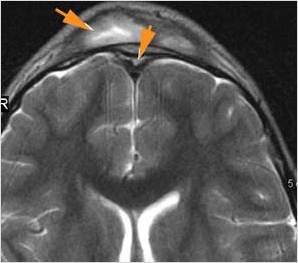

Intracranial

There is a subdural fluid collection or abscess along the boney walls of the anterior or middle cranial fossa.

There is a subdural fluid collection or abscess along the falx cerebri or within the tentorium.

There is brain edema specifically involving the frontal and temporal lobes.

There is cerebritis specifically involving the frontal and temporal lobes.